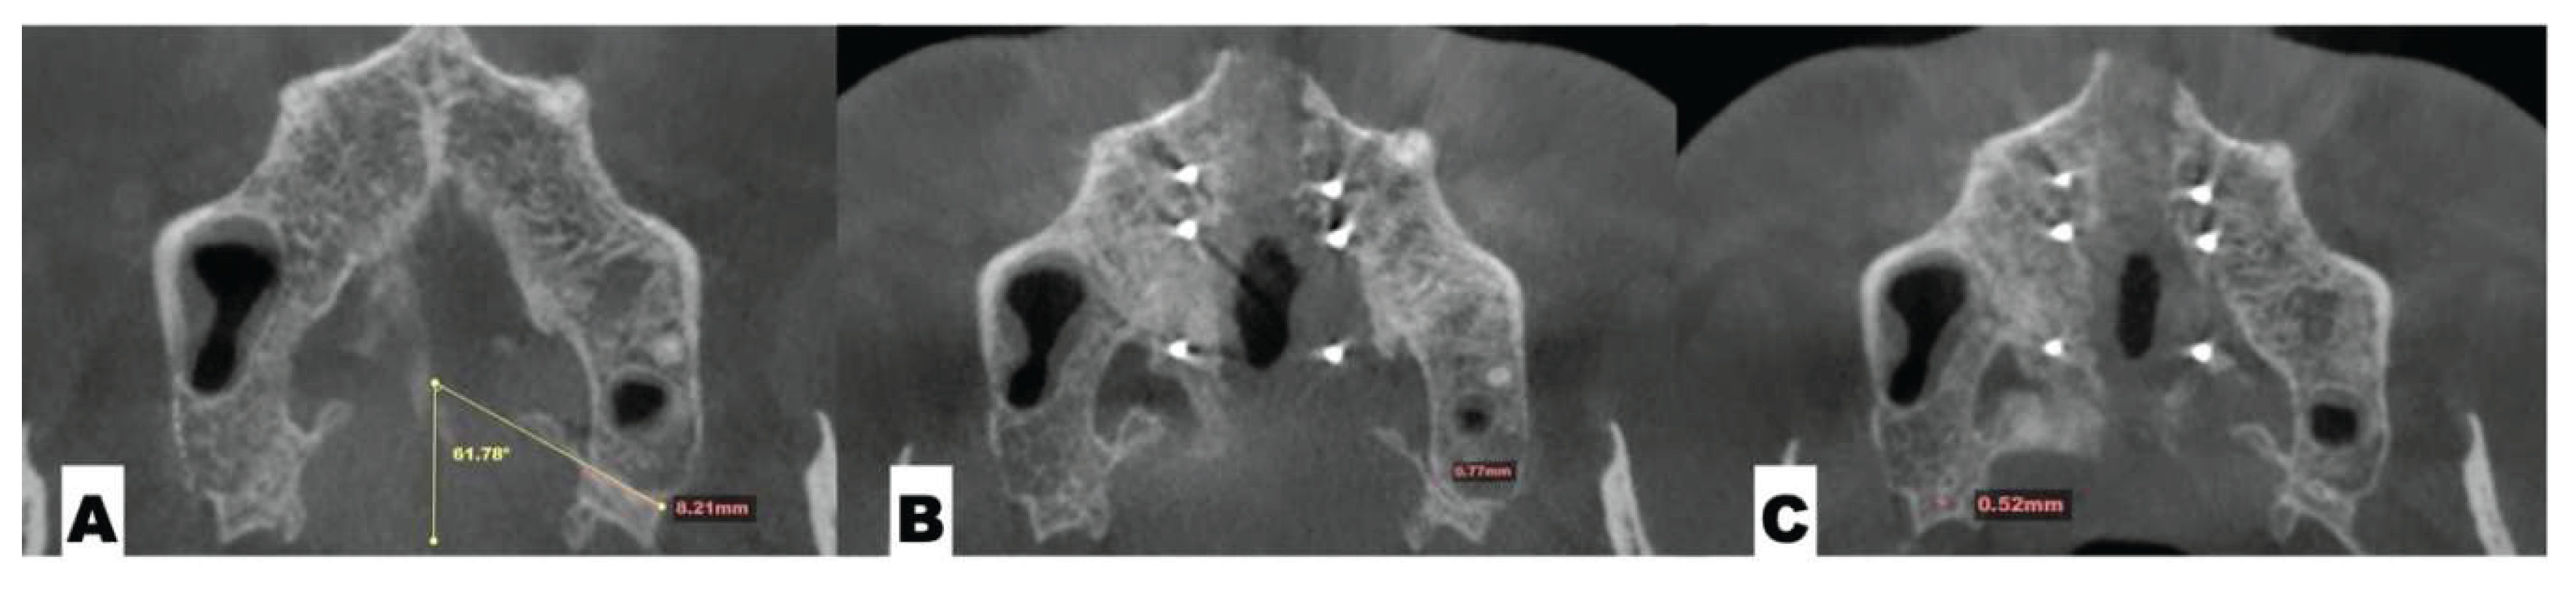

Background: While mini-screw-assisted rapid palatal expansion (MARPE) is effective for correcting maxillary transverse deficiency in adults, perimaxillary suture disarticulation—particularly at the pterygomaxillary junction—can be inconsistent. This study evaluates skeletal and dentoalveolar outcomes of a novel 3D-guided midpalatal piezocorticotomy-assisted MARPE protocol, focusing on expansion symmetry and pre-existing asymmetries. Methods: Three adult patients were retrospectively analyzed after treatment with 3D-guided midpalatal piezocorticotomy-assisted MARPE expansion and one with non-guided midpapalatal piezocorticotomy and MARPE expansion. Surgical guides were digitally designed using CBCT data to align with the nasal septum orientation in multiple planes. Perimaxillary suture disarticulation was measured pre- and post-expansion, and dentoalveolar changes were evaluated. Post-expansion asymmetries were addressed using directly printed aligners. Results: Complete midpalatal suture separation (mean 8.48 mm), involving both anterior and posterior nasal spine regions, was achieved in one patient. Bilateral pterygomaxillary disarticulation averaged 1.06–1.23 mm, resulting in forward–outward rotation of the nasomaxillary complex. Additional separation occurred at the frontonasal (2.03 mm) and vomeromaxillary (1–2 mm) sutures, with no significant changes in orbital or peri-orbital sutures. One patient presented with pre-existing dentoalveolar asymmetry, which intensified the perceived post-expansion imbalance but was successfully corrected with directly printed aligners. In the second case, 5.6 mm of suture separation resulted in a limited lateral nasal width increase (<1.5 mm), while maxillary base expansion exceeded 6 mm. A significant canine plane cant (1.2 mm) and divergent axial inclinations of the maxillary central incisors relative to the palatal plane were also observed. In the second case, a non-impactful palatal bone fracture with asymmetric displacement of the left palatine fragment was documented. After 16 months of aligner therapy, all cases exhibited favorable remodeling of the palatal structures, midpalatal suture, and alveolar processes, accompanied by improved dental alignment, occlusal plane symmetry, and mandibular dentoalveolar adaptation. The dento-alveolar expansion achieved in the third case over the course of 16 months of treatment was approximated at 4 mm. The fourth case showed consistent improvement with direct printed aligners after MARPE midpalatal diasrticulation of 11 mm after experiencing minor bone fracture. Conclusions: Human skulls exhibit considerable variability between the left and right sides, which can influence spatial balance. Pre-existing cranial asymmetries appear to be the primary contributors to asymmetry following MARPE treatment. Careful evaluation of dentoalveolar discrepancies and axial tooth inclinations is essential for preventing and managing potential asymmetric dental arch outcomes during the post-expansion phase. Although peri-maxillary bone fractures are relatively uncommon, their occurrence is influenced by multiple factors. Adjunctive techniques, such as 3D-guided midpalatal piezocorticotomy, show promise in significantly lowering the risk of intra-expansion peri-maxillary fractures.

| Suture nomenclature | Amount of disarticulation |

|---|---|

| Midpalatal | 8.48 mm |

| Palatinomaxillary (transverse) | none |

| Nasomaxillary | 1-2 mm |

| Zygomaticomaxillary | none |

| Lacrimomaxillary | none |

| Ethmoidomaxillary | none |

| Sphenomaxillary | none |

| Vomeromaxillary | 1-2 mm |

| Frontomaxillary | 2.5 mm |

| Pterygomaxillary | 1.06-1.23 mm |

| Frontonasal | 2.03 mm |

| Frontozygomatic | None |